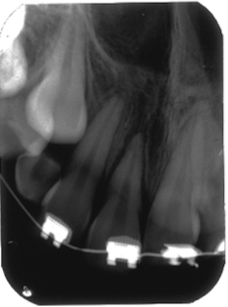

Tooth Injury comprises a group of clinical conditions that can have the separation or breakage of the tooth and its surrounding tissues. A case of multiple concomitant dental trauma is reported. In 2004, a female patient, 11 years old, visited the dental office a half hour after a dental trauma caused by a fall in the pool. She complained of mild discomfort in the tooth 11; in a clinical analysis, it was partially displaced from its socket and showed grade 2 mobility; in a radiographic analysis, the tooth showed an increase in the periodontal ligament space, a diagnosis of extrusive luxation. The adjacent teeth 21 and 22, presented subgingival bleeding, diagnosed with subluxation. After preparing the treatment plan, clinical approach consisted of manual reduction of the tooth 11 and non-rigid splint of affected teeth. The patient received a prescription of antibiotic and anti-inflammatory. After 15 days, the splint was removed and the teeth 11, 21 and 22 showed pulpal sensibility, maintaining the same results for 4 months. In the 4th month, tooth 11 was diagnosed with pulp necrosis, thus requiring endodontic treatment. After 10 years, teeth were asymptomatic, with a slight color change in tooth 11; the cone beam scan indicated root resorption in the apical third of the three elements and the presence of dystrophic calcification of teeth 21 and 22. In conclusion, the injured teeth remain in function with relevant follow-up period, highlighting the search for a response, upon the purpose of the study.